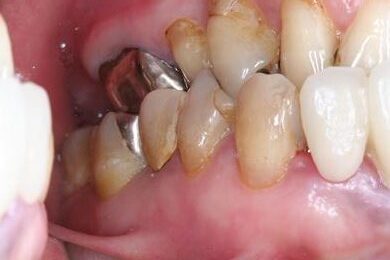

インプラントの症例写真 IMPLANT

インプラント治療+セラミック治療

| 治療内容 | インプラント3本、ジルコニアフレームオールセラミッククラウン7本(ジルコニア用土台1本)、メタルボンドセラミッククラウン3本(メタルボンド用土台3本)、ハイブリッドセラミッククラウン3本、ハイブリッドセラミックインレー3本 | ||||||||||||||||||||||||||||||||